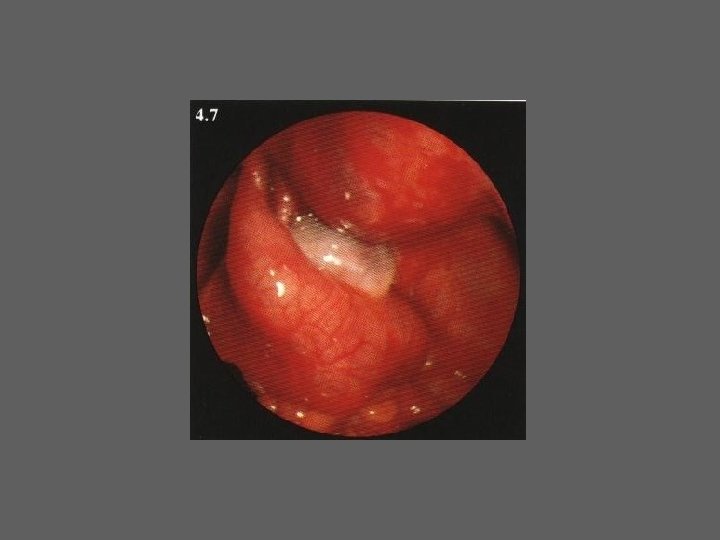

HISTEROSCOPIA - INDICAÇÕES Todas a situações em que se julgue vantajosa uma visualização completa da cavidade uterina, em particular: – Metrorragias – Dismenorreia adquirida – Infertilidade – Abortamentos de repetição e parto pré-termo – HSG anormal – DIU “perdido” – GIFT e ZIFT – Tratamento cirúrgico da patologia intracavitária: ● pólipos, miomas, septos, sinéquias, recessões endometriais ● baixos custos, reduzida morbilidade